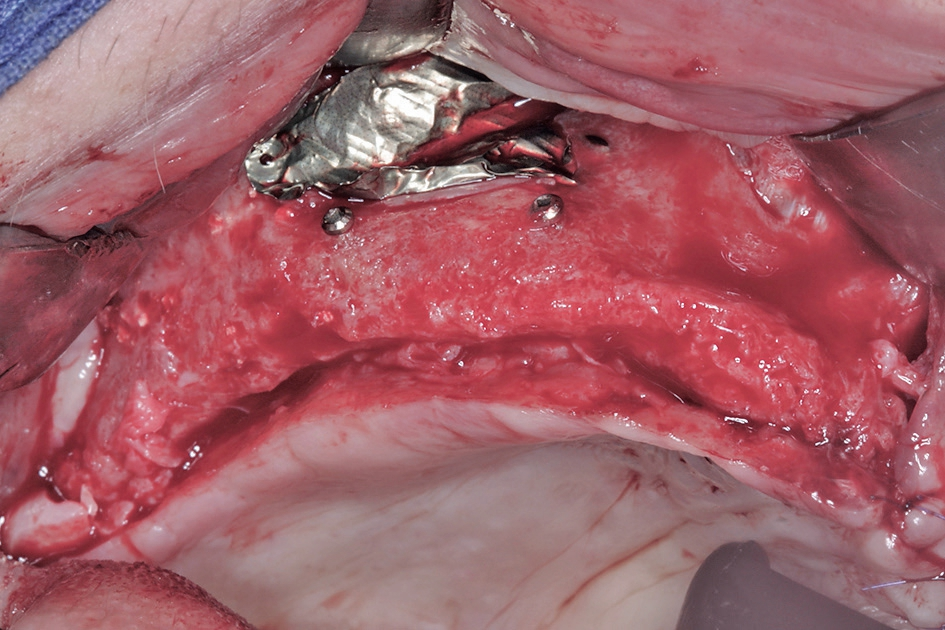

Den dritten und letzten chirurgischen Behandlungsschritt stellte die Freilegung der Implantate und Versorgung mit Gingivaformern dar. In diesem Fall wurde ein apikaler Verschiebelappen [5] präpariert, um den ursprünglichen anatomischen Verlauf der mukogingivalen Grenze wieder herzustellen und einstrahlende Bänder im periimplantären Bereich zu vermeiden (Abb. 19 bis 21). Nach 14 Tagen zum Zeitpunkt der Nahtentfernung sieht das Gewebe gewöhnlicherweise noch etwas „wild“ aus, weswegen man mit der Abformung besser 3 bis 4 Wochen nach der Freilegung warten sollte.